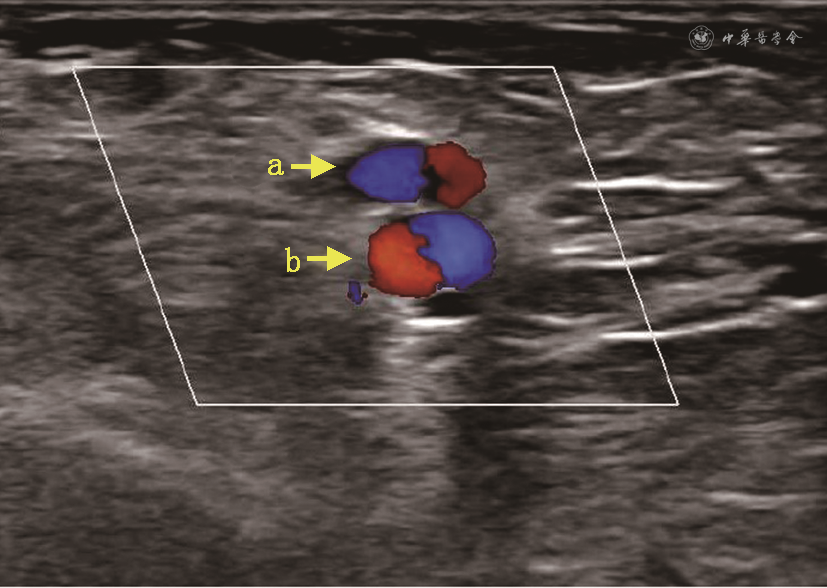

术前血管超声结果示63例患者流出静脉、流入动脉内径分别为(2.86±0.72)、(2.41±0.61)mm;术后2、4、8周超声结果示距吻合口5 cm处静脉内径分别为(4.82±0.84)、(5.22±0.86)、(5.64±1.13)mm,肱动脉血流量分别为(988±513)、(1 153±632)、(1 190±613)ml/min,血管距皮深度分别为(2.56±1.11)、(2.52±1.29)、(2.52±1.14)mm,静脉壁厚度分别为(0.64±0.18)、(0.65±0.14)、(0.69±0.16)mm。超声结果示术后流出静脉均匀扩张,静脉血管壁逐渐增厚,肱动脉血流量逐渐升高。术后2、4、8周进行超声评估时,83.3%(50/60)、91.7%(55/60)和90.7%(49/54)的患者流出静脉内径≥0.40 cm,83.3%(50/60)、90.0%(54/60)和88.9%(48/54)的AVF血流量>500 ml/min。彩色多普勒提示头静脉和桡动脉均呈现螺旋层流(图3)。

注:MNTT为完全“不接触”静脉血管处理技术;AVF为动静脉内瘘;箭头a示头静脉,箭头b示桡动脉

本研究中,通过MNTT建立的AVF血流动力学稳定。由于AVF几何构型的改变(包括动静脉的夹角、游离段的长度和游离静脉的扭转等),静脉血管摆动段(静脉剥离区域)血流动力学紊乱,大部分为湍流[16, 17]。同时,分离静脉和周围组织破坏了静脉的滋养血管和组织支撑,导致静脉壁缺血缺氧[18]。MNTT不改变静脉血管走形,静脉血管不会出现扭转,且动静脉夹角较小,同时完整地保留了静脉血管周围组织为静脉血管提供支撑和固定,避免血管摆动和湍流形成,彩色多普勒提示桡动脉和头静脉均呈现螺旋层流。